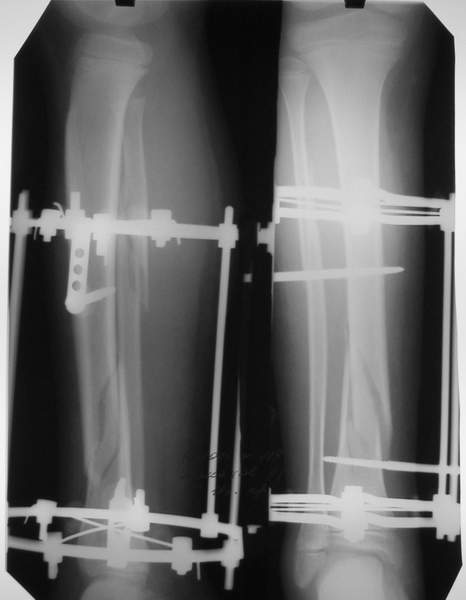

В аттачтах №№ 1 и 2 - примеры, когда 2 кольца не позволили послеоперационно

исправить смещение фрагментов большеберцовой (по ширине и вальгусное).

А казалось бы (#2) - поиграй на штангах и все влетит.

1

1a

2

3a

3b

3c

В аттачте № 3 - один из примеров полукольцевого аппарат...

Это уже я баловался.

Итог? Работы больше (по времени и

интраоп "подгонке"), срастается также, а особого преимущества по сравнению с

"чиста" кольцевым (вес, удобство ношения и пр.) - я, по крайней мере,

не нашел.

Теперь не балуюсь.